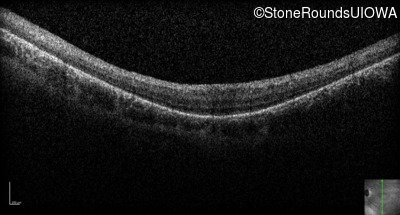

Optical Coherence Tomography - Left - 20/100

Exemplar / OCT Stack

OCT Stack